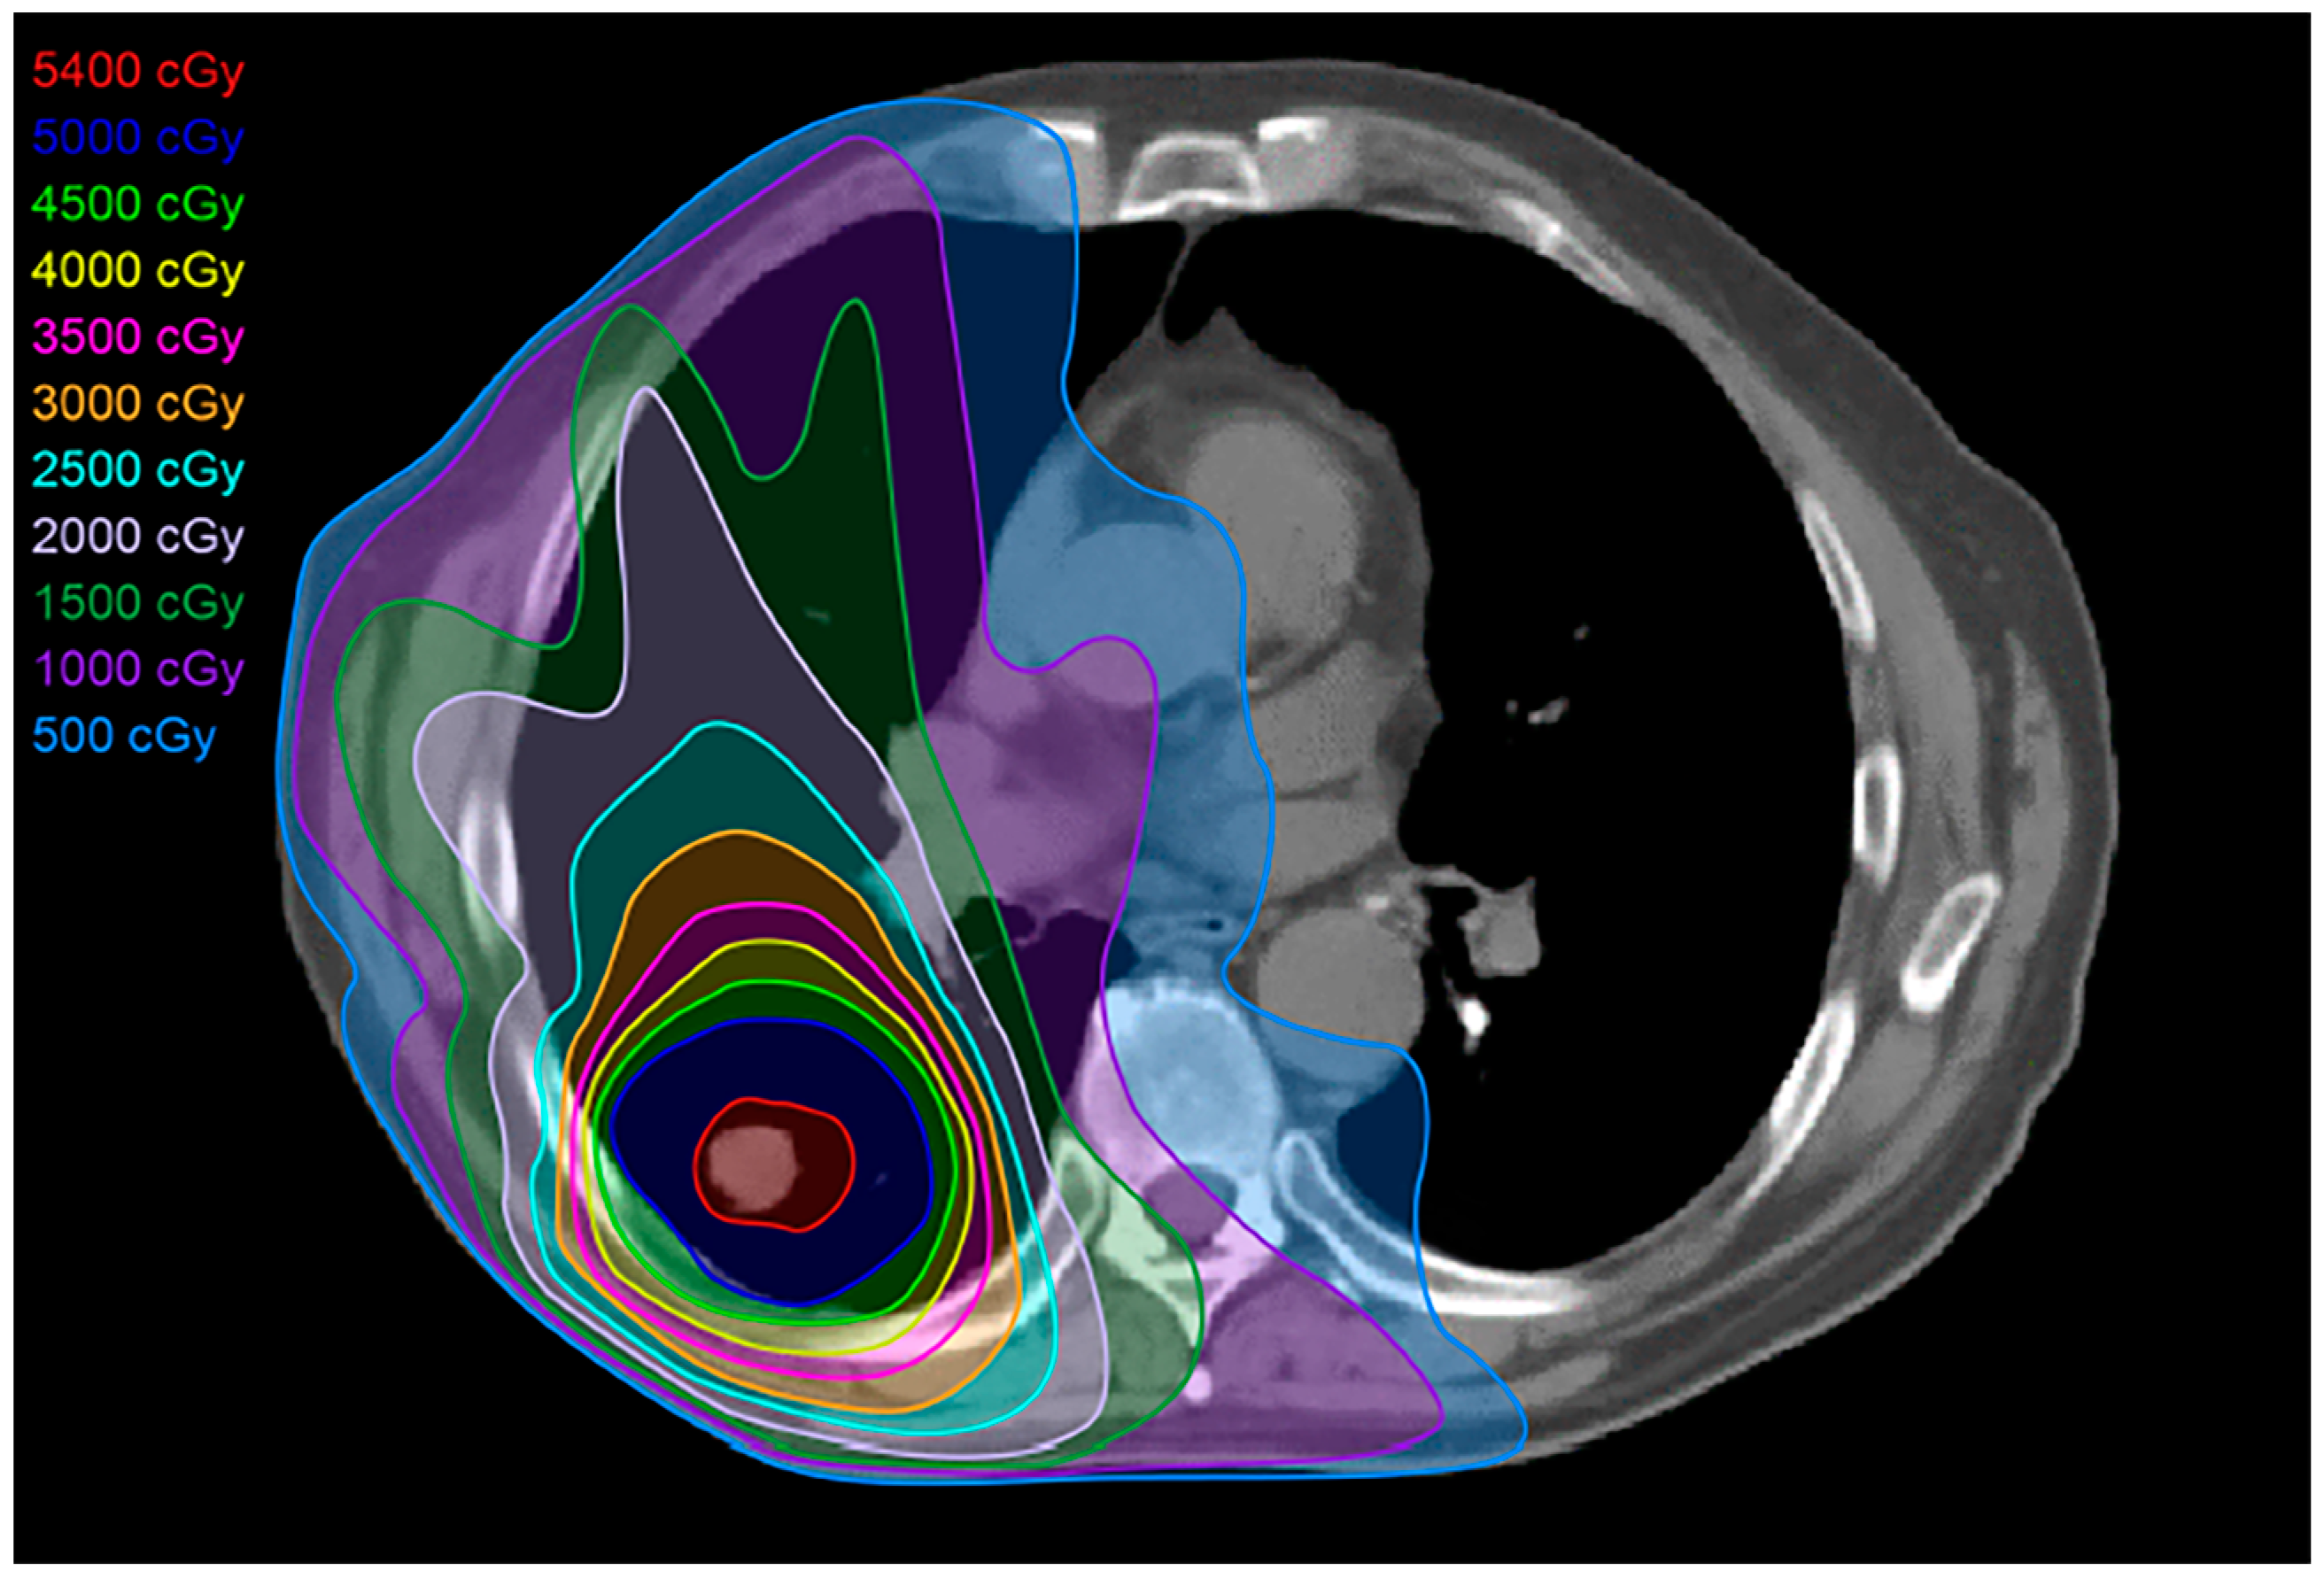

2.2. Three-Dimensional Conformal Radiotherapy

2.3. Intensity-Modulated Radiotherapy